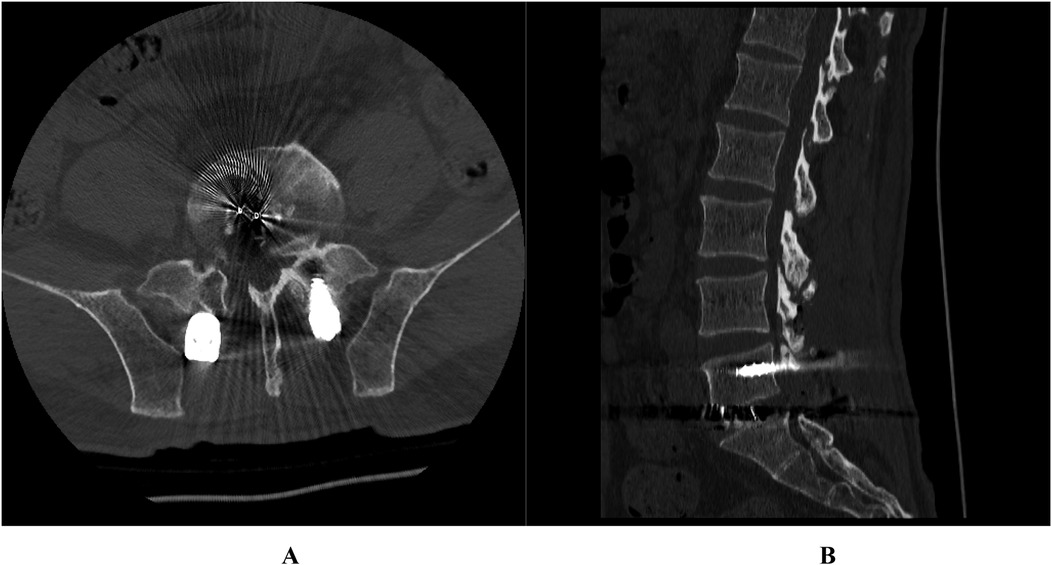

Posterior marginal osteophytes at the vertebral level are frequently observed in individuals with lumbar disc herniation (LDH); however, complete encasement of the nerve root by such osteophytes is exceedingly uncommon. We present two cases of surgical management of vertebral posterior marginal osteophytes completely encasing the nerve root. This report examined two cases of LDH accompanied by vertebral posterior marginal osteophytes completely encasing the nerve roots. Both patients underwent spinal canal decompression, discectomy, and intervertebral fusion. Postoperatively, varying degrees of nerve root injury were noted. By the 3-month follow-up, marked recovery in neurological function was achieved in both cases. The presence of vertebral posterior marginal osteophytes completely encasing the nerve root represents a notable risk factor for nerve root injury in LDH cases. Tailored surgical approaches are imperative to minimize complications and optimize patient outcomes.